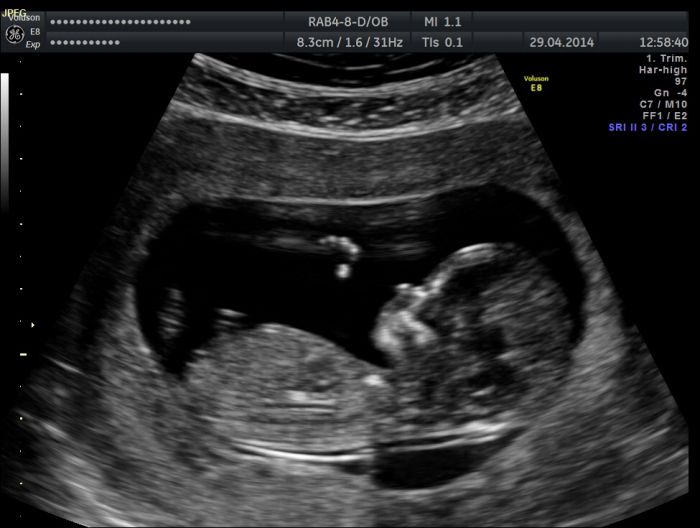

Autor: Zofie   1.5.2014 v 08:07

Snazim se vlozit foto z utz.